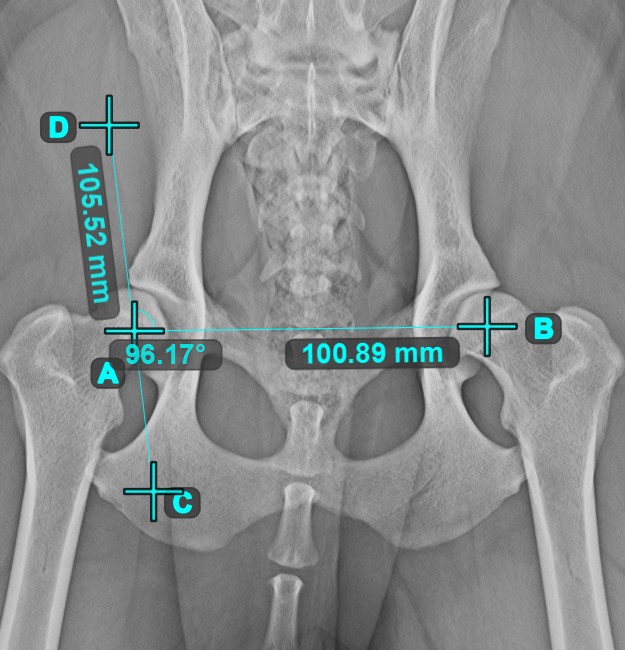

Measurement Point¶

Measurement Point

tool. Each point is assigned with a letter for better identification.Select/Move Item

tool. Select the point by using the assigned mouse button of the tool, and then move it freely anywhere on the image.